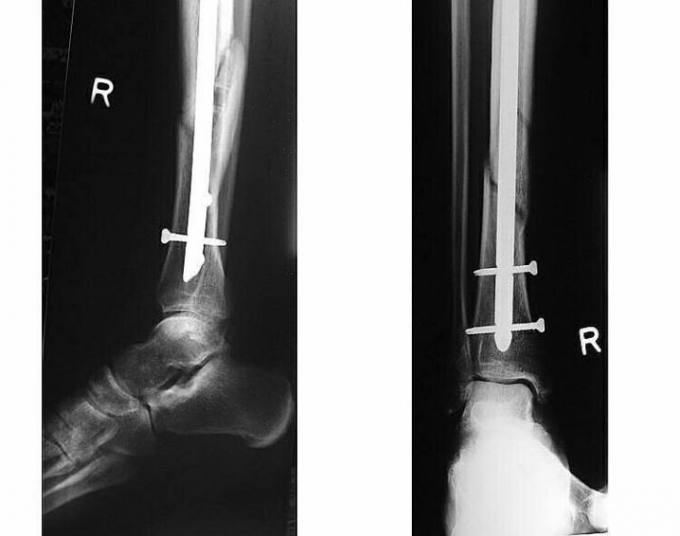

這是當地Ospedale Civile di Urbino醫院

傳來的術後X光照片.醫生表示手術非常成功

依照目前的傷勢.至少需要40天的靜養.短期將無法參賽

在進行完右腿脛骨和腓骨的固定手術後.